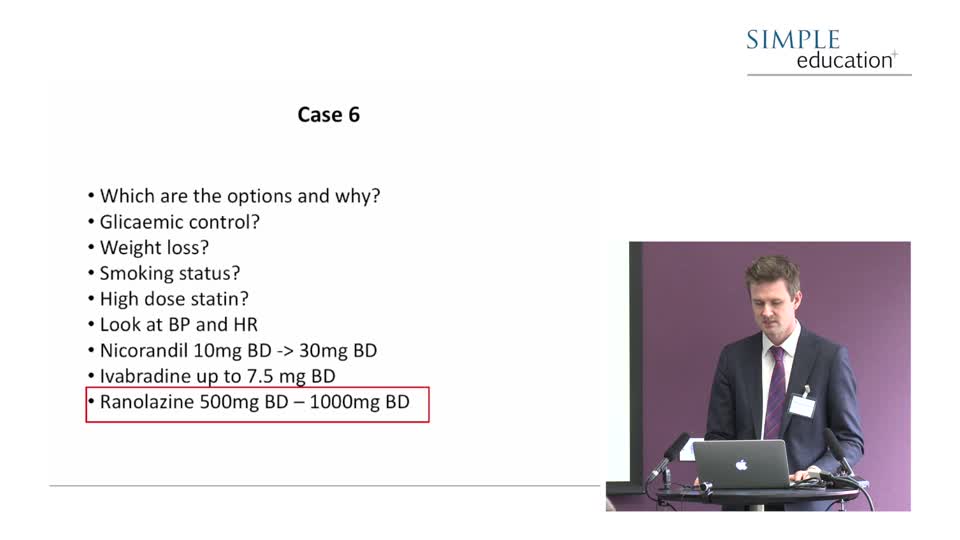

Revascularisation in stable angina: a contemporary perspective - Dr Rasha Al-Lamee